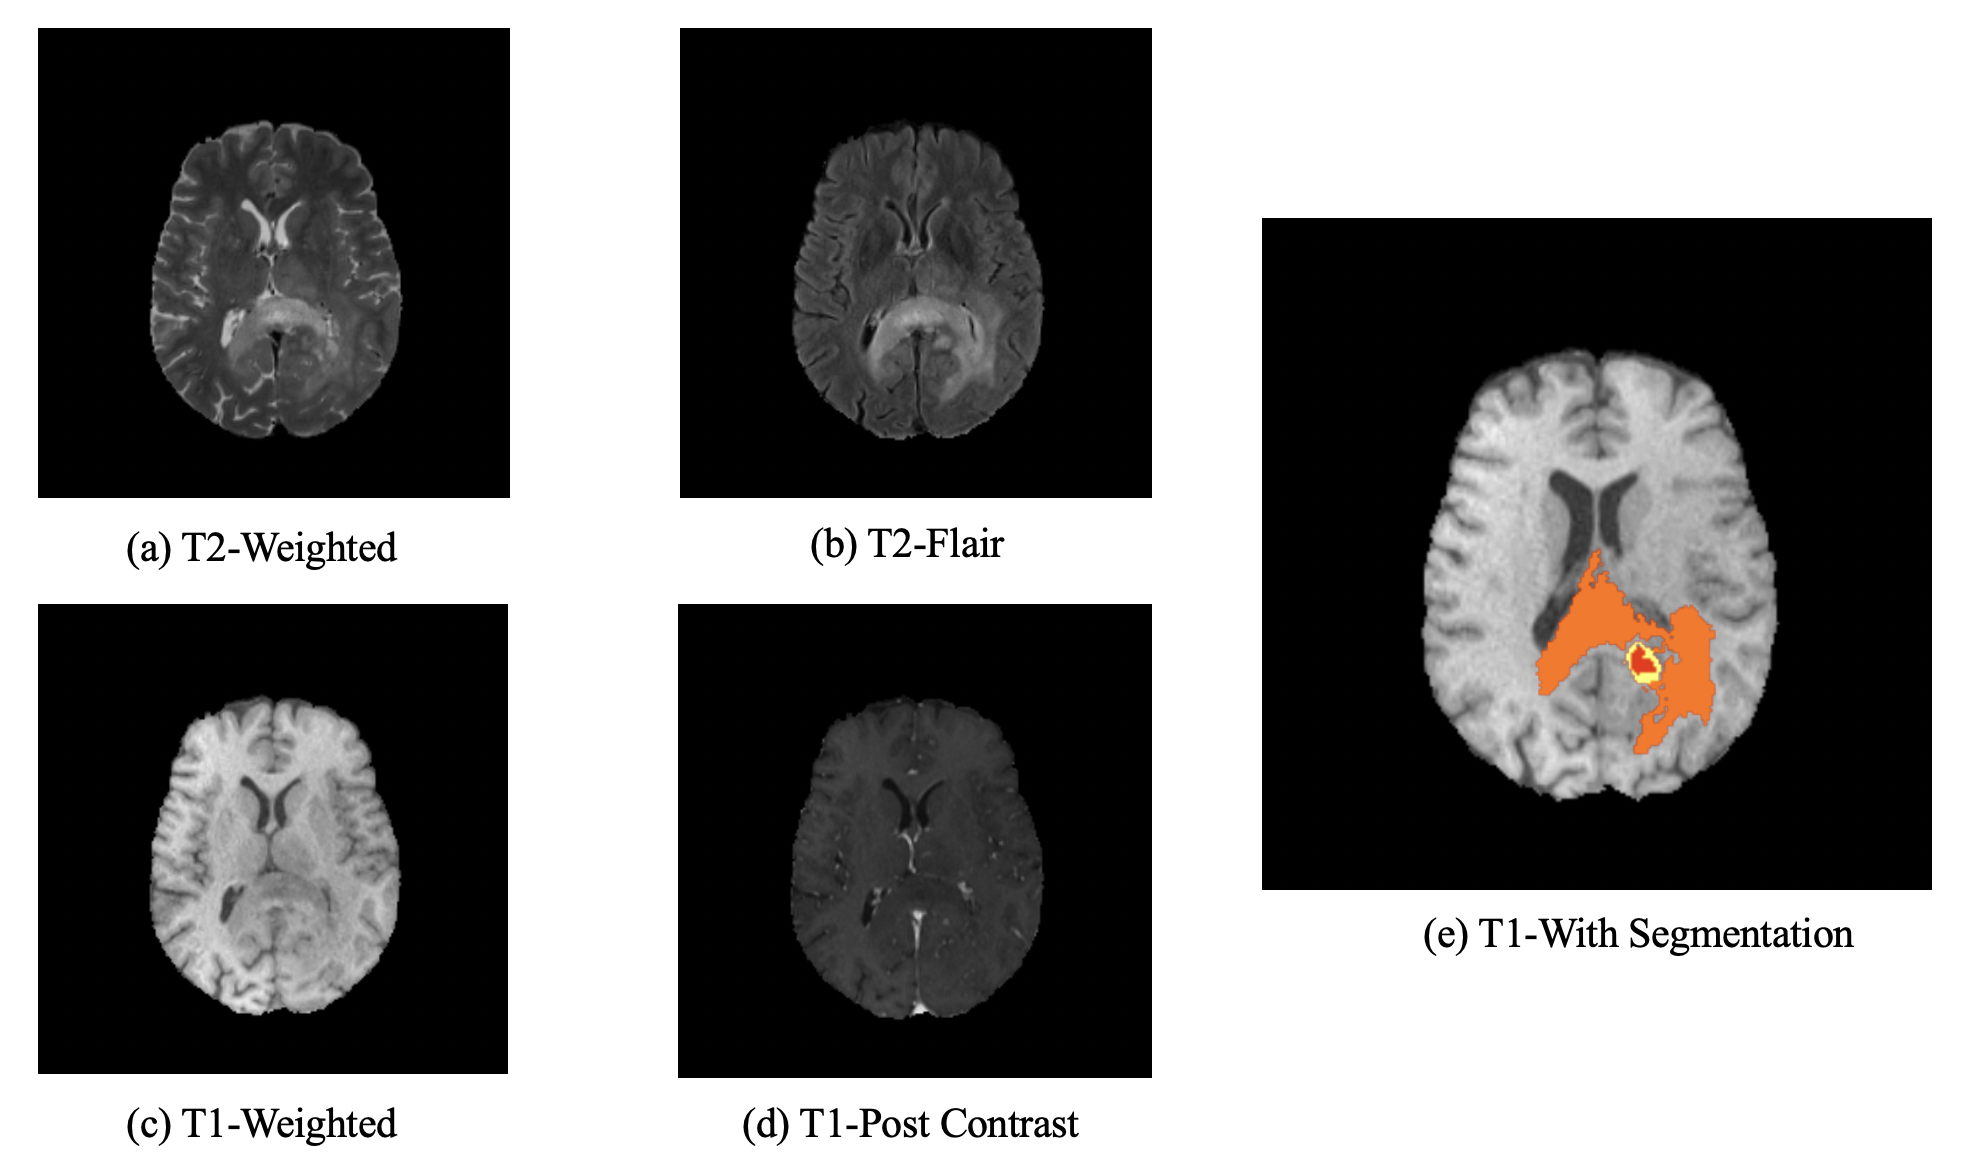

The Multimodal Brain Tumor Segmentation Challenge (BraTS) is an annual international competition that aims to evaluate state-of-the-art methods of brain tumor segmentation [1, 2, 3, 13]. The organizer provides a 3D multimodal MRI dataset with “ground-truth” tumor segmentation labels annotated by physicians and radiologists. For each patient, four 3D MRI modalities are provided including native T1-weighted (T1), post-contrast T1-weighted (T1c), T2-weighted (T2), and T2 Fluid Attenuated Inversion Recovery (T2-FLAIR) volumes. The brain tumor segmentation task concentrates on three tumor sub-regions: the necrotic and non-enhancing tumor (NCR/NET, labeled 1), the peritumoral edema (ED, labeled 2) and the GD-enhancing tumor (ET, labeled 4). Fig. 1 shows an image set of a patient. The rankings of competing methods for this segmentation task are determined by metrics, including Dice score, Hausdorff distance (95%), Sensitivity, and Specificity, evaluated on the testing dataset for ET, tumor core (TC=ET+NCR/NET), and whole tumor (WT=TC+ED) [4].